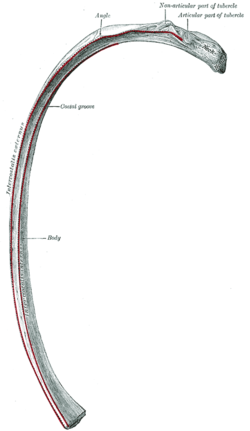

Side view of human rib cage. Seen are the 5-12 spareribs under lean muscle.